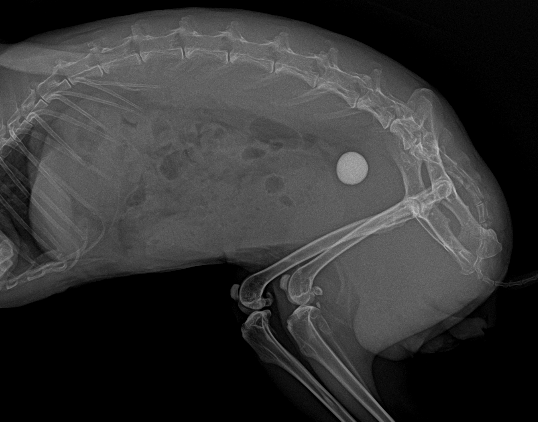

超音波検査では膀胱内に結石がみられました。レントゲン検査にて個数と、他の場所にも結石がないかどうか確認をしました。